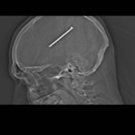

Nagel ins Hirn geschossen und nichts gemerkt

Album: Nagel ins Hirn geschossen und nichts gemerkt

AP

Datum: 22.01.2012

Besitzer: Stephanie Jiménez

Größe: 6 Elemente

Betrachtungen: 8